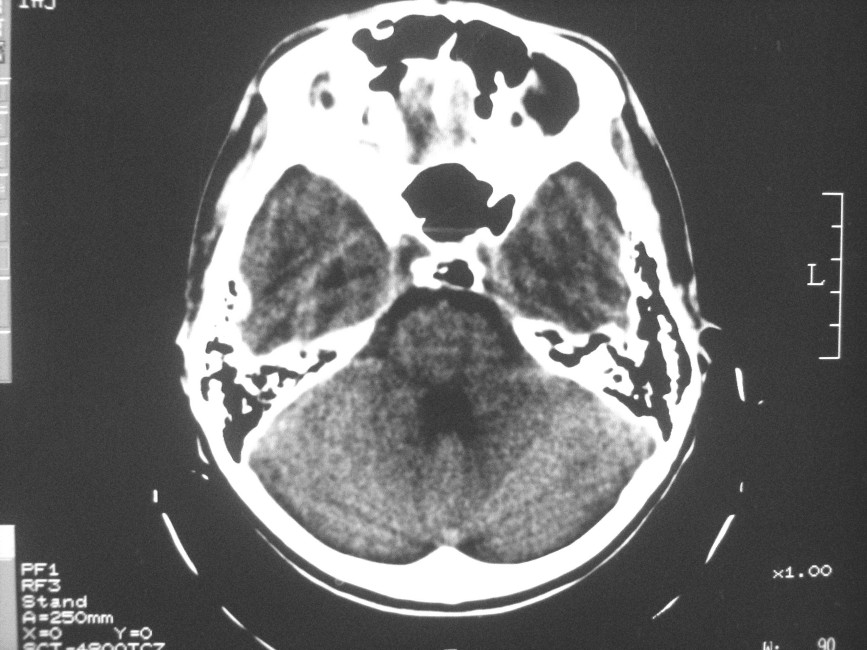

以下是引用zzyy在2008-6-16 10:13:00的发言:[br]两侧脑白质呈对称性密度减低,病儿有发热及脑膜刺激征。考虑急性病毒性脑炎。